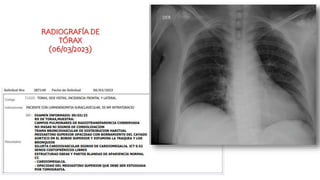

RADIOGRAFÍA DE

TÓRAX

(06/03/2023)